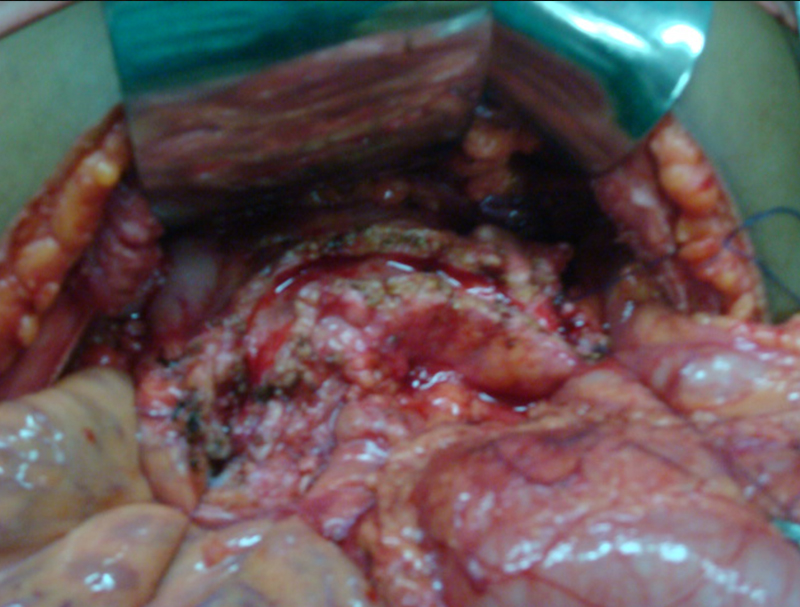

25 year old male presented with abdominal pain due to chronic calcific pancreatitis. He had had multiple previous endoscopic stent placement procedures & external shock wave treatment (ESWL) attempts to break & remove pancreatic stones and pancreatic duct stenting. He was investigated and later operated. A Frey procedure was done wherein the inflamed and stone filled core in the head of pancreas was removed, duct was widely opened along the head, neck, body and tail of pancreas. All the ductal stones were removed and multiple narrowing were opened. A loop of intestine was then joined with the pancreatic duct. He recovered uneventfully. He is fine for last 8 years and has not required any long term painkillers or had any episodes of pancreatitis. His dose of pancreatic enzyme supplements has also come down.